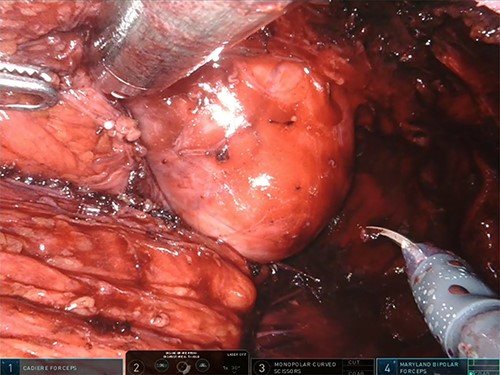

After uterus suspension and opening the presacral plane, a large mesorectal lipoma arising into the right posterolateral rectal wall was visualized (Fig. 3). Modest citrine free fluid in the Douglas pouch was collected and addressed to cytology, which was negative for malignant tumor cells. The muscolaris propria and mucosa were not involved by the lesion. The high precision of robotic surgery allows to move nimbly in the pelvis and avoid rupture of the lipoma capsule. Specimen extraction by an endoscopic bag from a Pfannenstiel scar was performed and the reported weight of the tumor was 600 g.